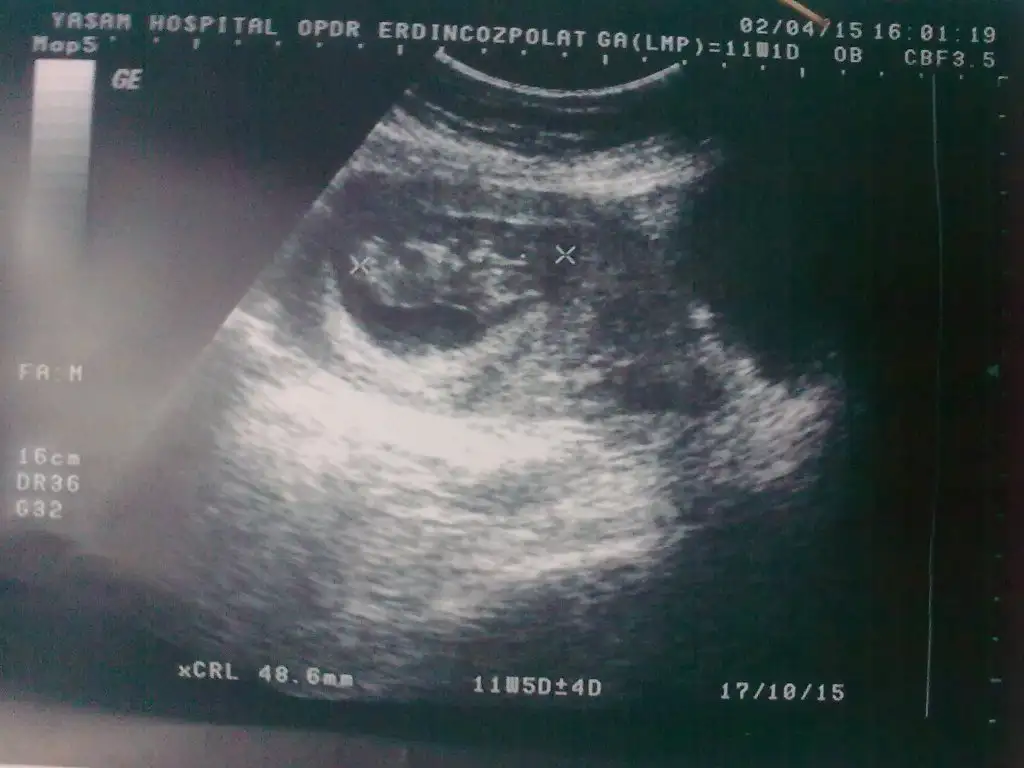

Kızlar çok yoğunum yazamıyorum kusura bakmayın. Hamile olan goamıydı hayırlı olsun Rabbim gönlüne göre versin inşallah. Kese fotosu atan eyhammıydı bebeği keseye göre erkek kese içinde sağda bebek çünkü. Bu dr remzi teorisiymiş. Test atan arkadaş inan testlerden anlamıyorum ama testte hata daha yüksek bence ağrı ve ateşe göre yaptıysan daha mantıklı yapmışsın. Asosyalci bebeğin foto koy bakalım belki biz yorum yaparız. Şuan okadar yoğunum isimler vs karıştı ama neyi kime yazdığımı anlar herkes inşallah

Eklentiler

• Görüntü1879.webp

Görüntü1879.webp

21,5 KB · Görüntüleme: 150